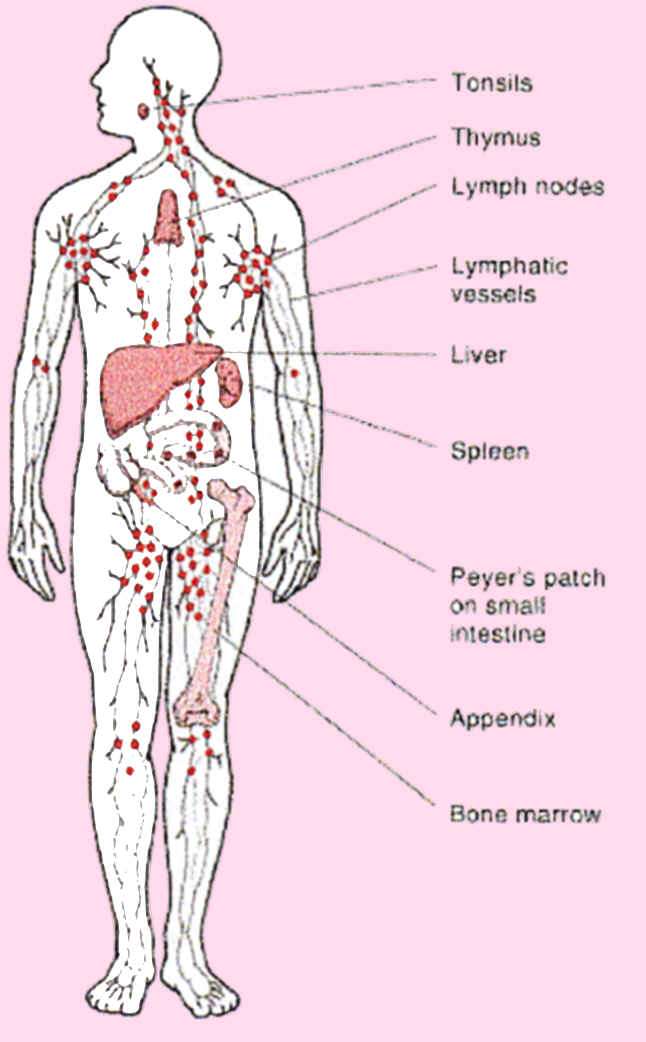

lymph nodes body node glands located lymphatic part they throughout small

lymph lymphatic nodes